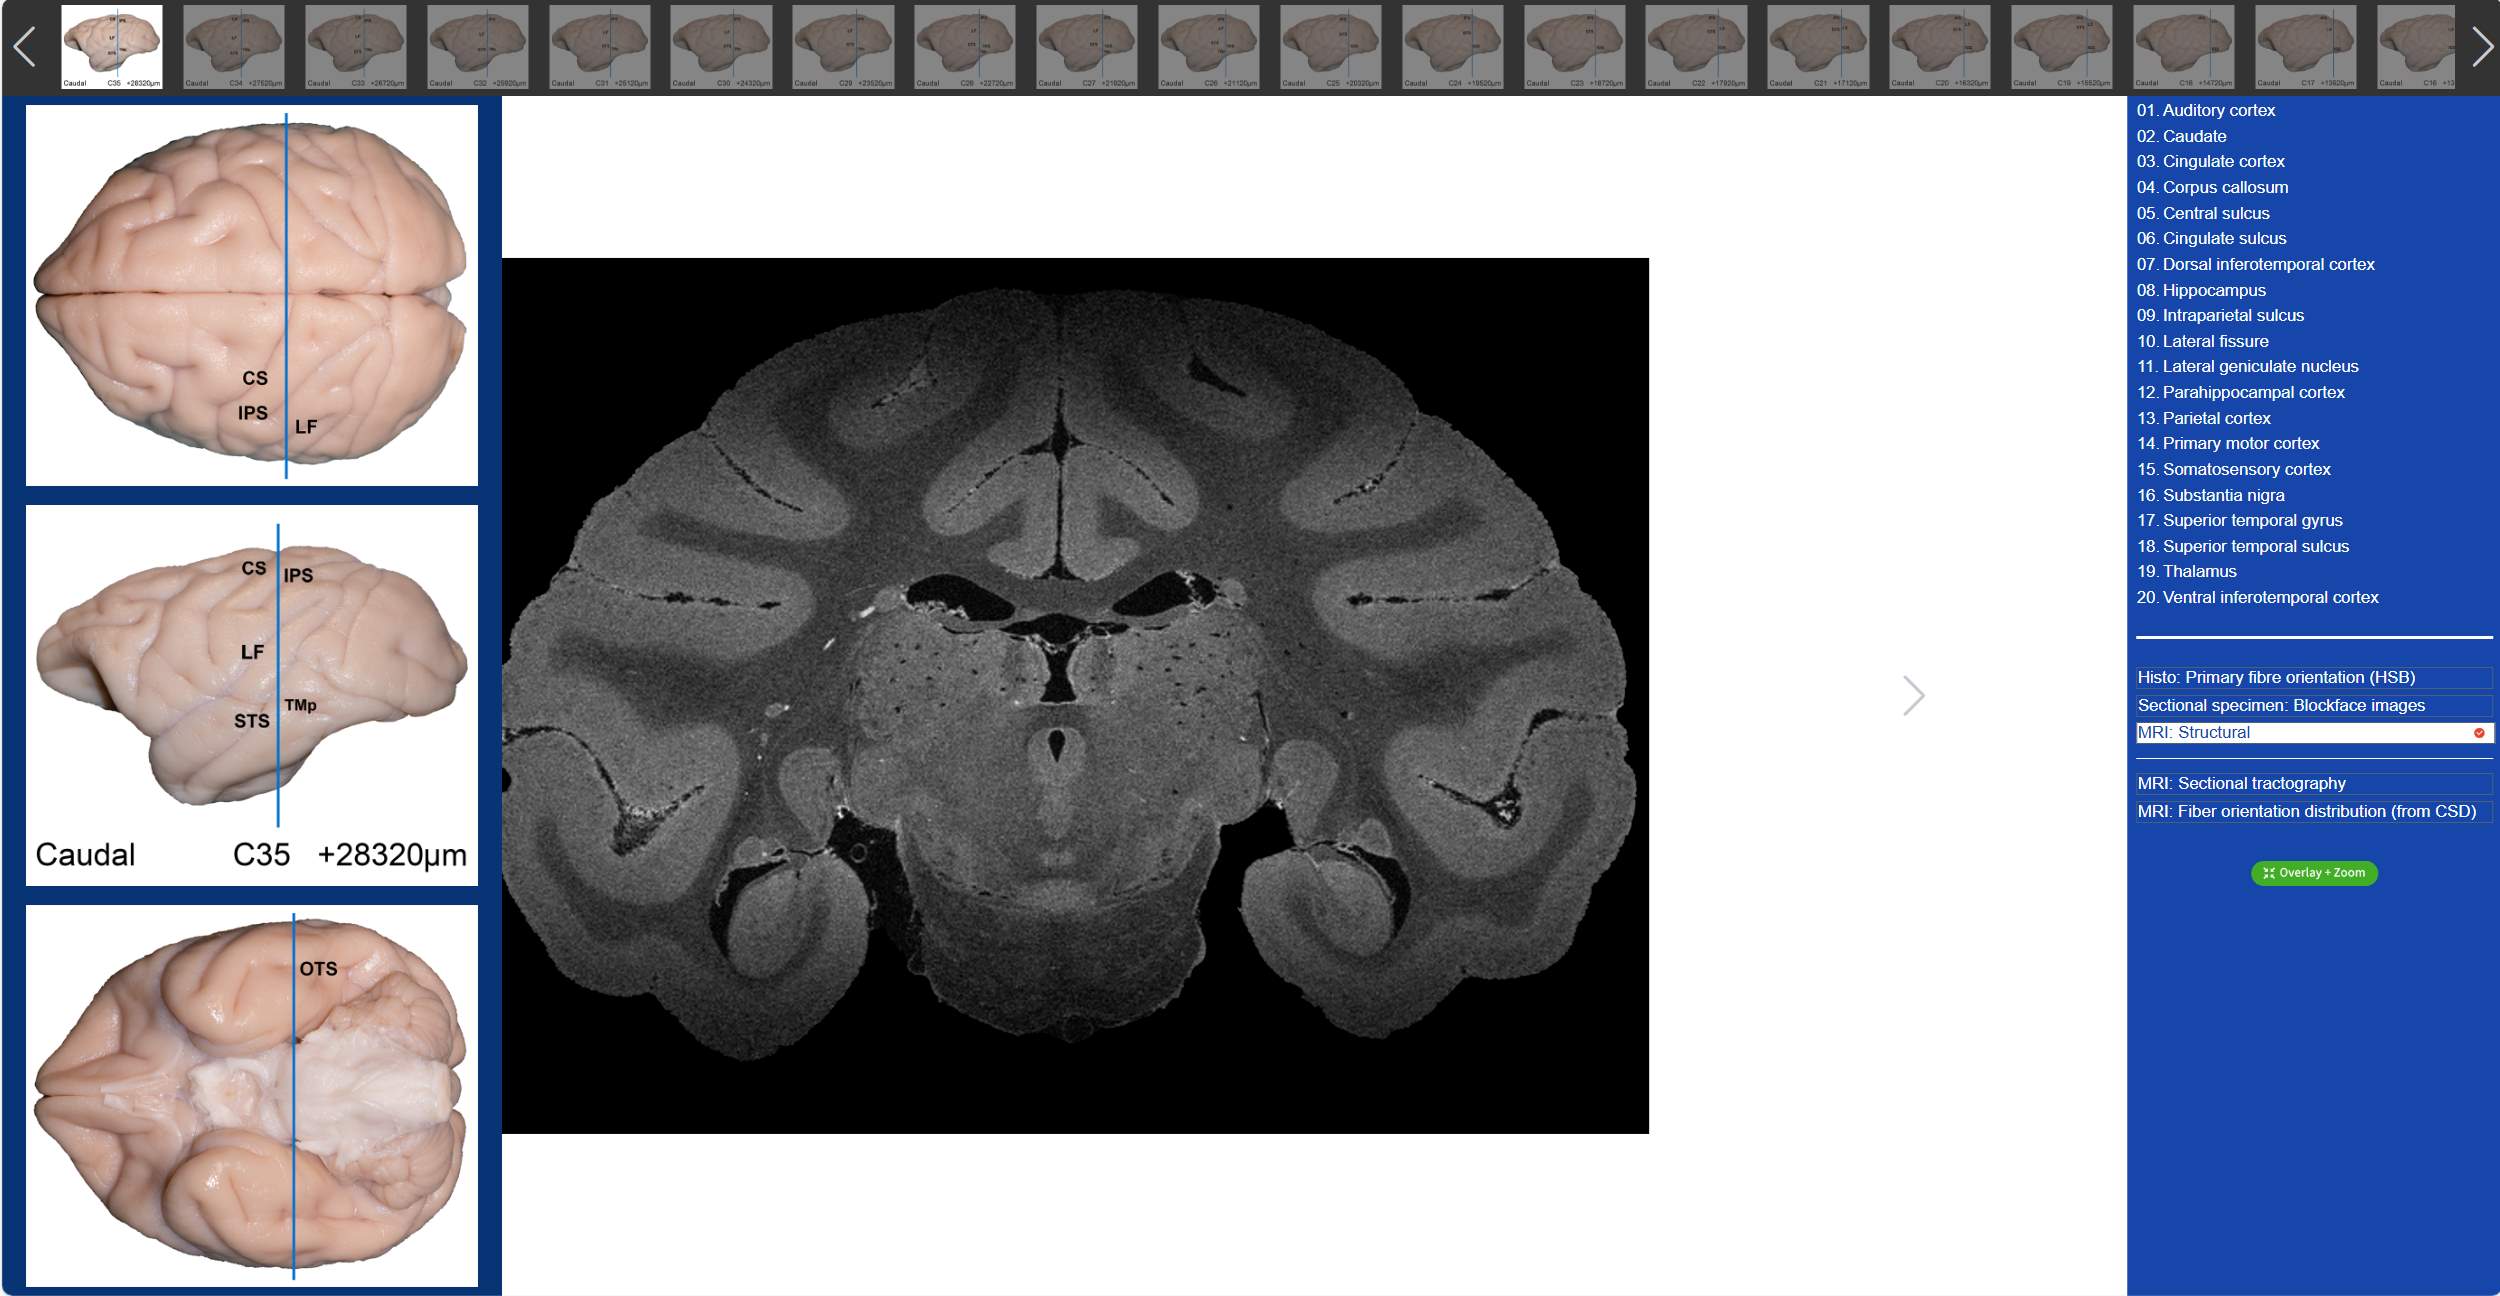

值得一提的是,在“動(dòng)物腦樂園”里,不僅可以觀察到獼猴3D腦標(biāo)本,還可以看到獼猴的全腦切片。吳勁松教授團(tuán)隊(duì)從同一猴腦的離體MRI及全腦組織切片髓鞘染色(LFB)數(shù)據(jù)集中,間隔800μm取一層,構(gòu)建了集合組織切片髓鞘染色(LFB)、組織切片髓鞘染色-偽彩化、斷層標(biāo)本圖、高分辨率MRI結(jié)構(gòu)像及離體腦dMRI斷層纖維束成像和纖維方向分布圖(限制球面反卷積-CSD)六大模態(tài)的斷層對(duì)照?qǐng)D譜。我們只需要點(diǎn)擊相應(yīng)的解剖名稱,就可以在圖譜上對(duì)應(yīng)位置顯示標(biāo)記,同時(shí)可與另外兩大模態(tài)的dMRI方向性信息進(jìn)行對(duì)照,極大的方便了我們的觀看。